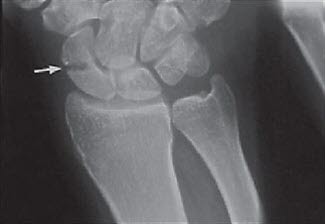

Etter skaden oppstår straks smerter. Ofte er det ikke noen hevelse, men det kan blø litt i vevet (du blir blå på skadestedet etter noen dager). Legen får mistanke til tilstanden både ut fra hvordan skaden oppstod, dine smerter og funn som gjøres ved undersøkelsen. Typisk vil det fremkalle smerter hvis man klemmer i "snusdåsen" ved roten av tommelen - skafoidbeinet ligger like under huden her. Røntgen vil kunne bekrefte at det foreligger brudd (se røntgenbilde).

Men noen ganger kan man ikke se bruddforandringer på røntgen ved den første undersøkelsen. Dersom mistanken om at det foreligger brudd, er stor, vil det legges på en gips, og du blir bedt om å komme tilbake etter 2 uker til kontroll. Da fjernes gipsen, og det tas nye røntgenbilder. På dette tidspunktet er det større mulighet for at et eventuelt brudd vises på røntgen. I noen tilfeller må man ty til MR-undersøkelse, eventuelt scintigrafi, for å avsløre bruddet.